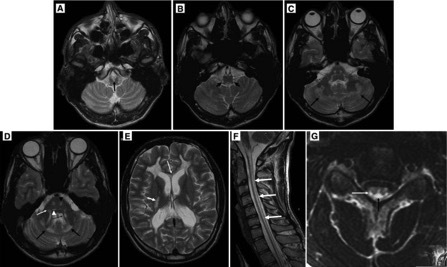

20、多发性硬化:多发性硬化(MS)的临床特征是神经功能障碍的缓解与恶化。起病因素包括感染,创伤,怀孕,情感压力和过敏反应。临床上确诊为MS的患者中有70%〜95%的患者有MRI异常表现,MRI的发现已经成为诊断MS的一个重要因素。MS累及脑干及脊髓通常见于年轻患者。在尸检中,MS病灶通常散在分布于大脑、脑干、脊髓及脑灰白质中。

横断位T1WI示脑桥右前方小低信号灶,横断位T2WI及矢状位、横断位T2WI FLAIR示病灶呈高信号,横断位T1WI抑脂后增强示病灶轻微强化,DWI示弥散受限。